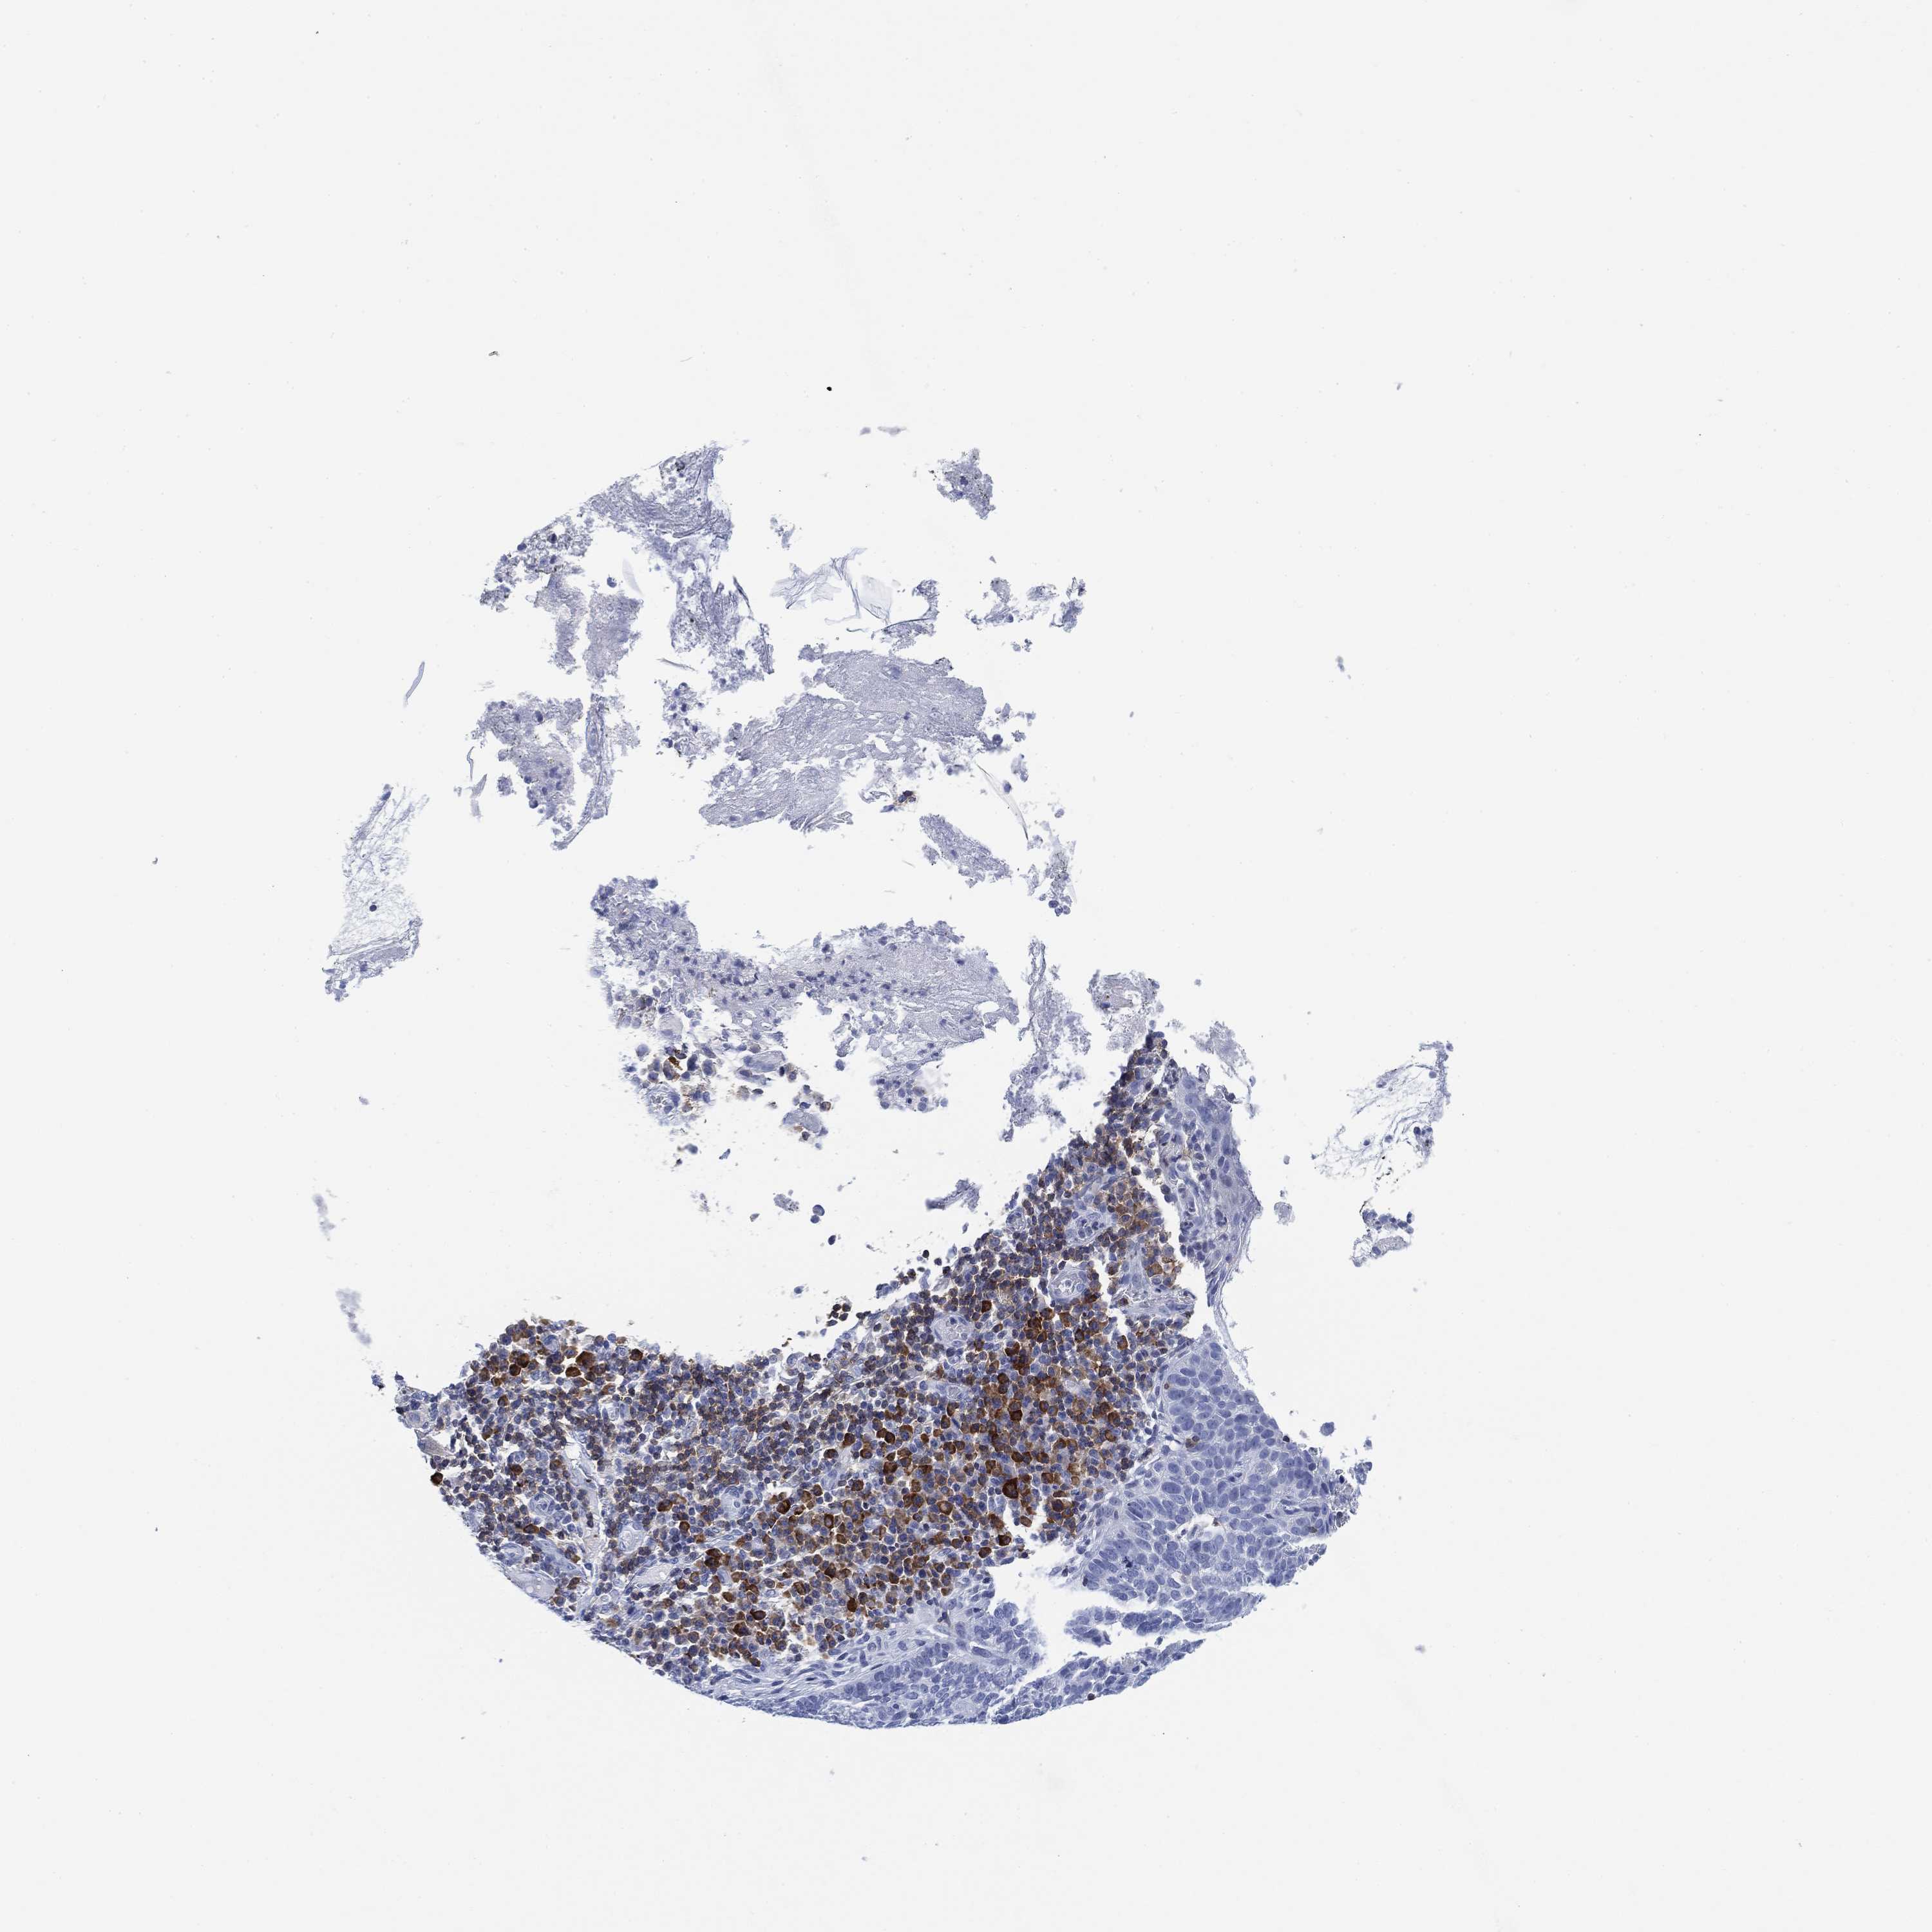

SKIN CANCER - Protein expressioni

A mouse-over function shows sample information and annotation data. Click on an image to view it in a full screen mode. Samples can be filtered based on level of antibody staining by selecting one or several of the following categories: high, medium, low and not detected. The assay and annotation is described here.

Antibody staining in the annotated cell types in the current human tissue is reported as not detected, low, medium, or high, based on conventional immunohistochemistry profiling in selected tissues. This score is based on the combination of the staining intensity and fraction of stained cells.

Each image is clickable and will lead to virtual microscopy that enables deeper exploration of all samples and also displays staining intensity scores, fraction scores and subcellular localization as well as patient and tissue information for each sample.

Antibody HPA067427

Squamous cell carcinoma, NOS